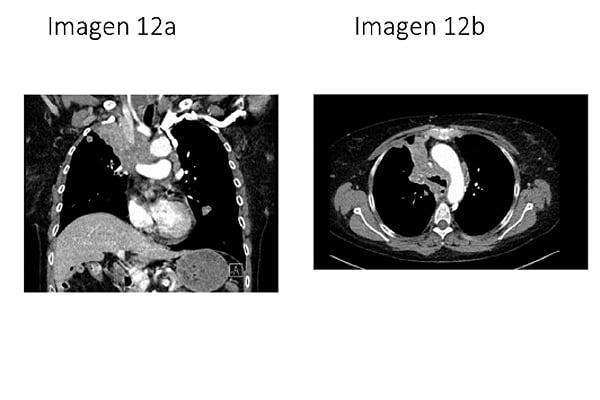

12. Paciente de 70 años fumador de 2 paquetes de cigarrillos al día. Acude a urgencias por disnea, plétora facial, edema en esclavina y cianosis. Se realiza una Tomografía axial computerizada (TAC) de tórax en el que se observan las siguientes imágenes (IMAGEN 12a y 12b). ¿Cuál es el diagnóstico más probable?:

-

Carcinoma microcítico de pulmón.

Linfoma de Hodgkin.

Metástasis de carcinoma no microcítico de pulmón.

Carcinoma tímico.